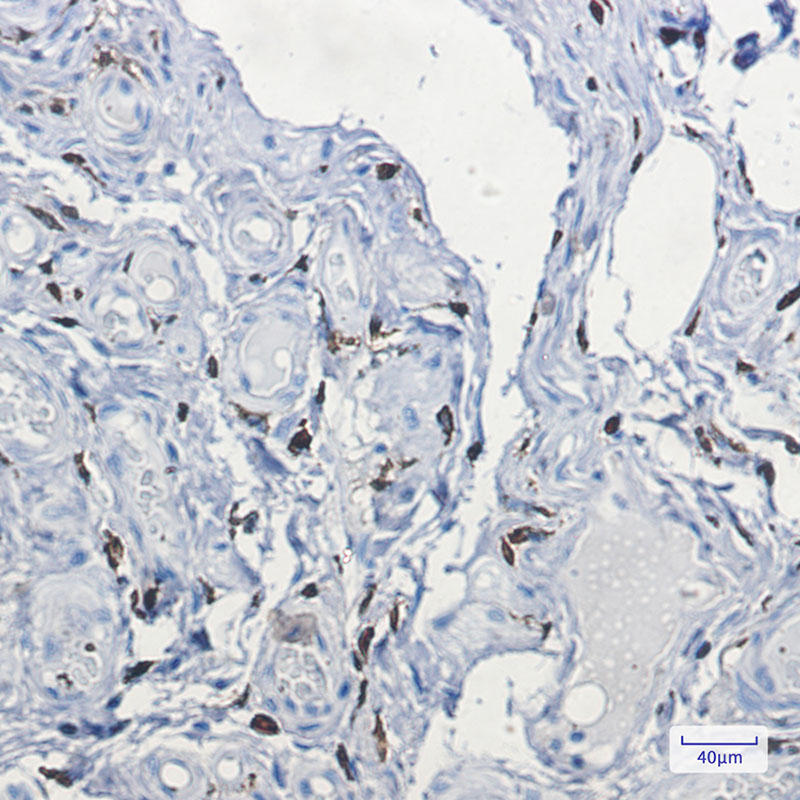

Product Image

IHC | 1/50-1/100 |